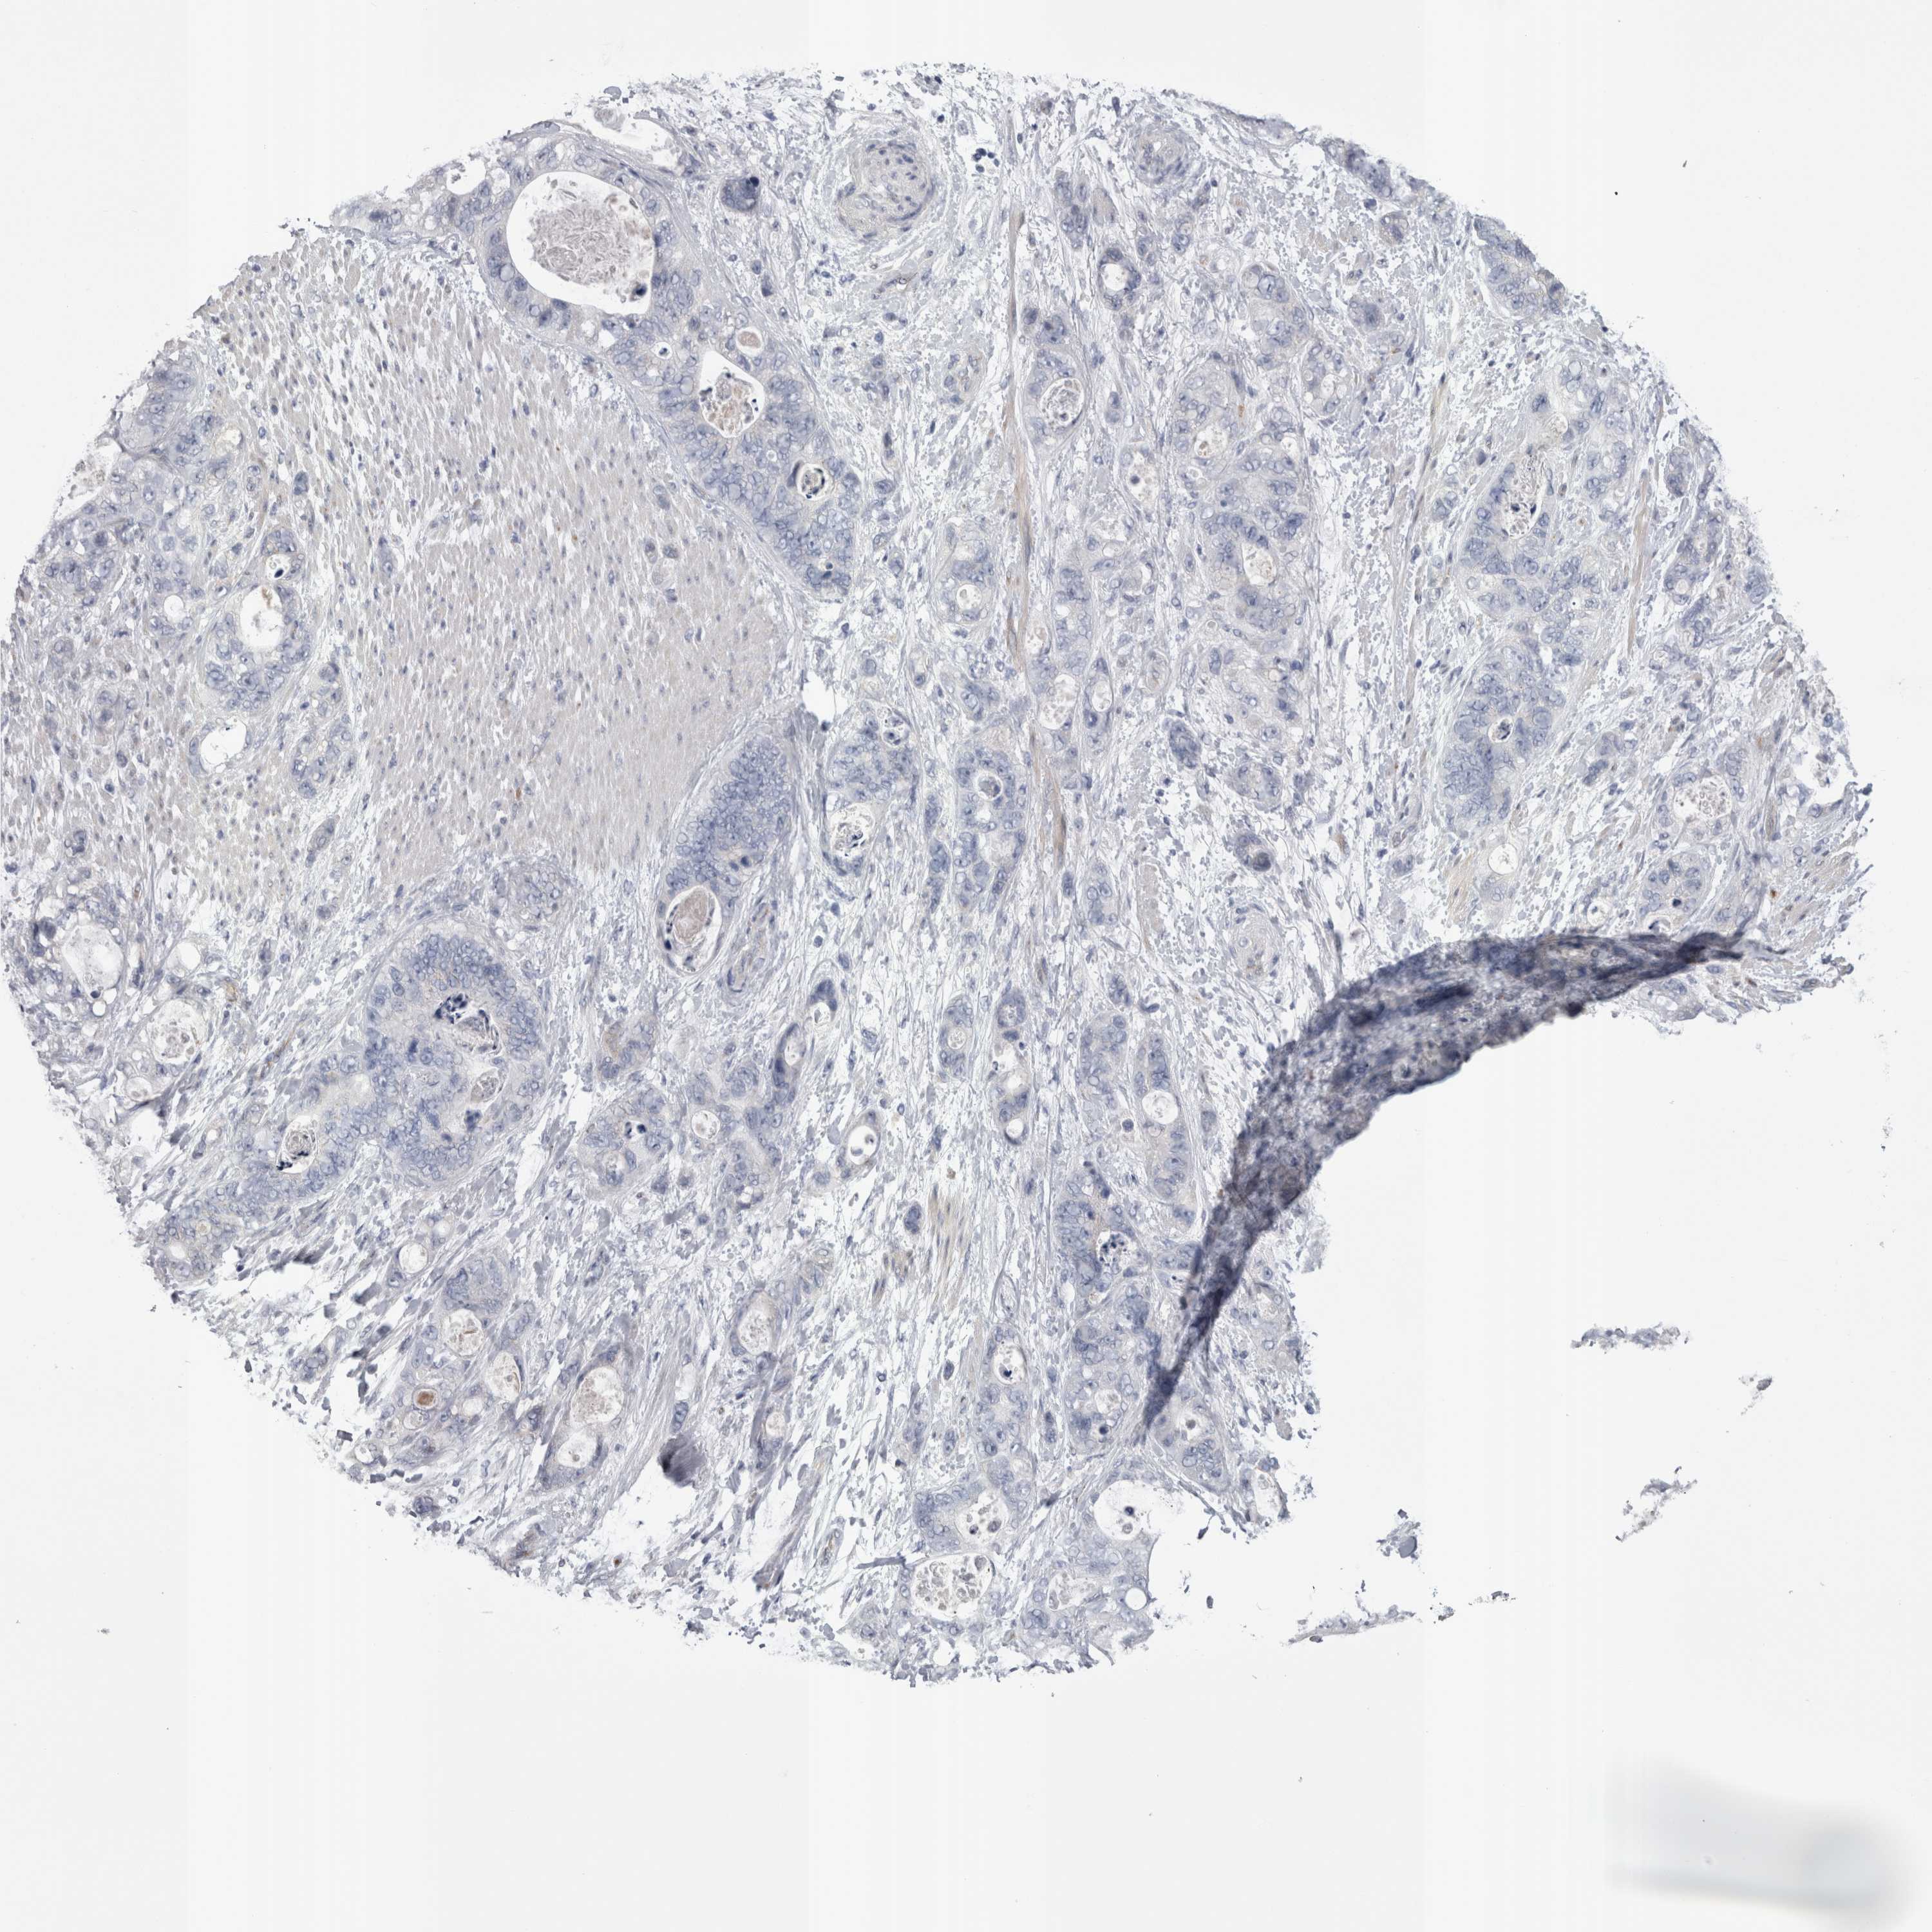

STOMACH CANCER - Protein expressioni

A mouse-over function shows sample information and annotation data. Click on an image to view it in a full screen mode. Samples can be filtered based on level of antibody staining by selecting one or several of the following categories: high, medium, low and not detected. The assay and annotation is described here.

Note that samples used for immunohistochemistry by the Human Protein Atlas do not correspond to samples in the TCGA dataset.

Antibody stainingi

Antibody staining in the annotated cell types in the current human tissue is reported as not detected, low, medium, or high, based on conventional immunohistochemistry profiling in selected tissues. This score is based on the combination of the staining intensity and fraction of stained cells.

Each image is clickable and will lead to virtual microscopy that enables deeper exploration of all samples and also displays staining intensity scores, fraction scores and subcellular localization as well as patient and tissue information for each sample.

Antibody HPA023918

Antibody CAB018625

Staining

High

Medium

Low

Not detected

Intensity

Strong

Moderate

Weak

Negative

Quantity

>75%

75%-25%

<25%

None

Location

Nuclear

Cytoplasmic/membranous

Cytoplasmic/membranous,nuclear

Adenocarcinoma, NOS